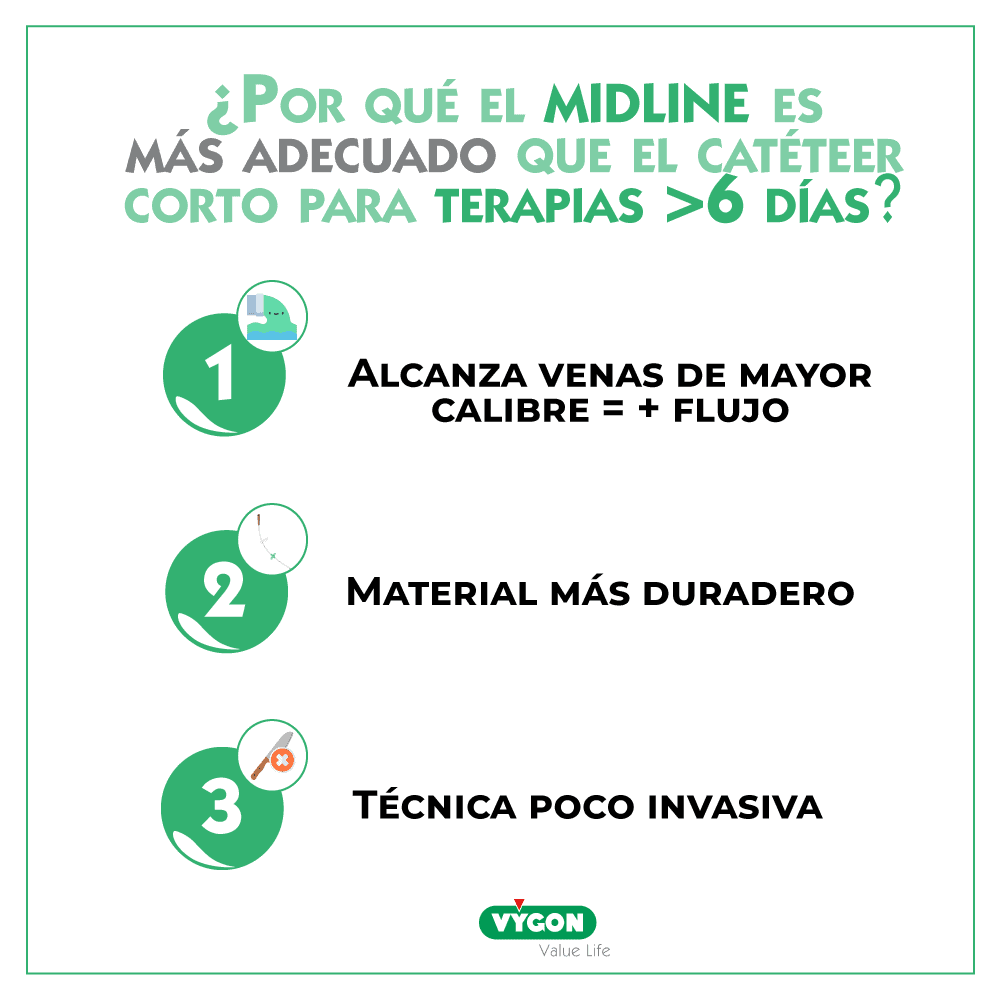

El catéter corto es una vía de corta duración que permite la perfusión de tratamientos con una duración < 7 días. Para un tratamiento superior y por las limitaciones que supone es necesario considerar una alternativa que permita al profesional sanitario no irse a una vía central, recurso innecesario para una terpapia periférica.

El catéter de línea media representa hoy en día la mejor solución en estos contextos y también para pacientes DIVA (con muy poco acceso venoso). En este post te explicamos qué es.

- al ser de material más duradero (poliuretano) permite mantener la misma vía para todo el tratamiento

- su técnica de inserción (Seldinger) es poco invasiva y reduce las complicaciones inmediatas

- la ecografia que acompaña la inserción permite elegir la mejor vena y adecuar el diámetro del catéter a la vena. Lo cual reduce las complicaciones como la flebitis y la trombosis

- al ser un catéter insertado en venas profundas alcanza un flujo importante que permite una administración adecuada de la medicación.

Frente a las limitaciones del catéter corto periférico, la línea media permite un acceso vascular periférico que facilita el acceso a un calibre de vena suficiente grande como para evitar las complicaciones relacionadas con una localización muy periférica de la punta del catéter (flebitis, extravasación).

Se trata de un catéter que ofrece una mayor durabilidad y así se pueden reducir los pinchazos.

Ofrece una técnica de inserción lo menos invasiva posible, lo que ayuda a prevenir las complicaciones tempranas: edema, hematoma, malfuncionamiento del catéter, etc.

Para terapias no hiperosmolares y con pH entre 5 y 9, superiores a 6 días, las guías internacionales recomiendan el uso de la línea media.